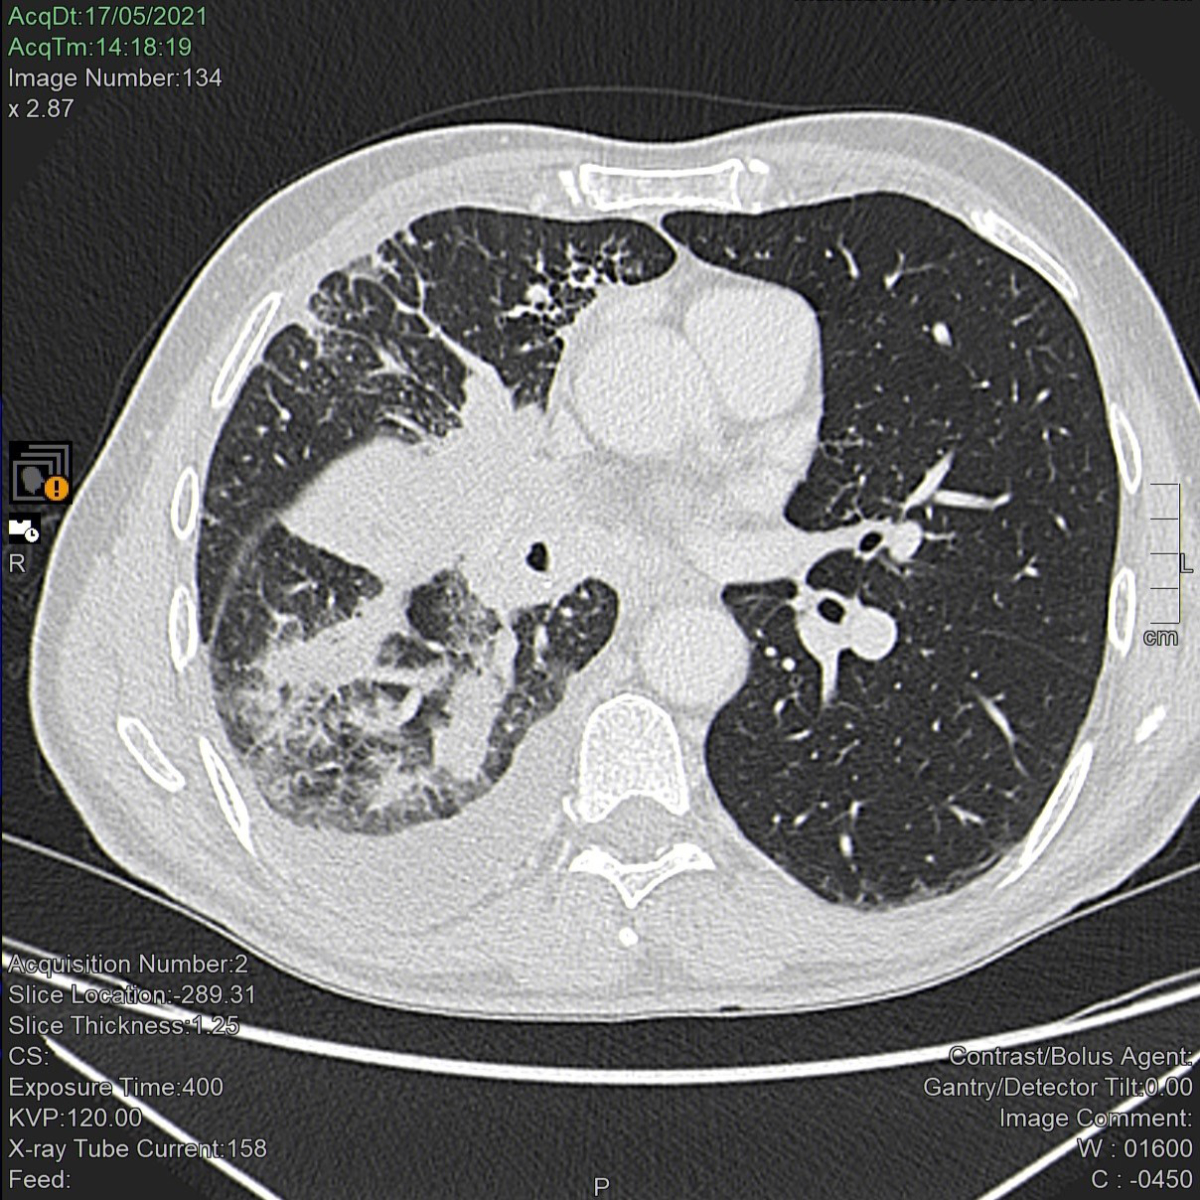

The patient started first-line immunotherapy with pembrolizumab (Keytruda®) 200 mg every three weeks on June 21, 2021. After the fourth pembrolizumab dose (800 mg cumulative dose), the patient had an optimal antitumour response (figures 1 and 2) but developed hypothyroidism (thyroid-stimulating hormone levels 30.04 mIU/l; normal values [n.v.] 0.5–5.0 mIU/l). Replacement therapy with levothyroxine 75 mcg per day was prescribed. Concurrently, the patient reported upper limb myalgia and muscle weakness, exacerbation of his chronic eczema with new areas of skin involvement, and moderate dyspnoea on exertion.

Figure 1Computed tomography scan of the lungs before treatment with pembrolizumab. A neoplastic mass occupies the right hilum causing complete stenosis of both the middle lobar bronchus (with complete atelectasis of the middle lobe) and the segmental apical bronchus of the lower right lobe. The lower lobar bronchus is reduced in size, parenchymal localizations are visible in the lower lobe and lymphangitis is apparent in the upper lobe. Pleural effusion is also apparent.